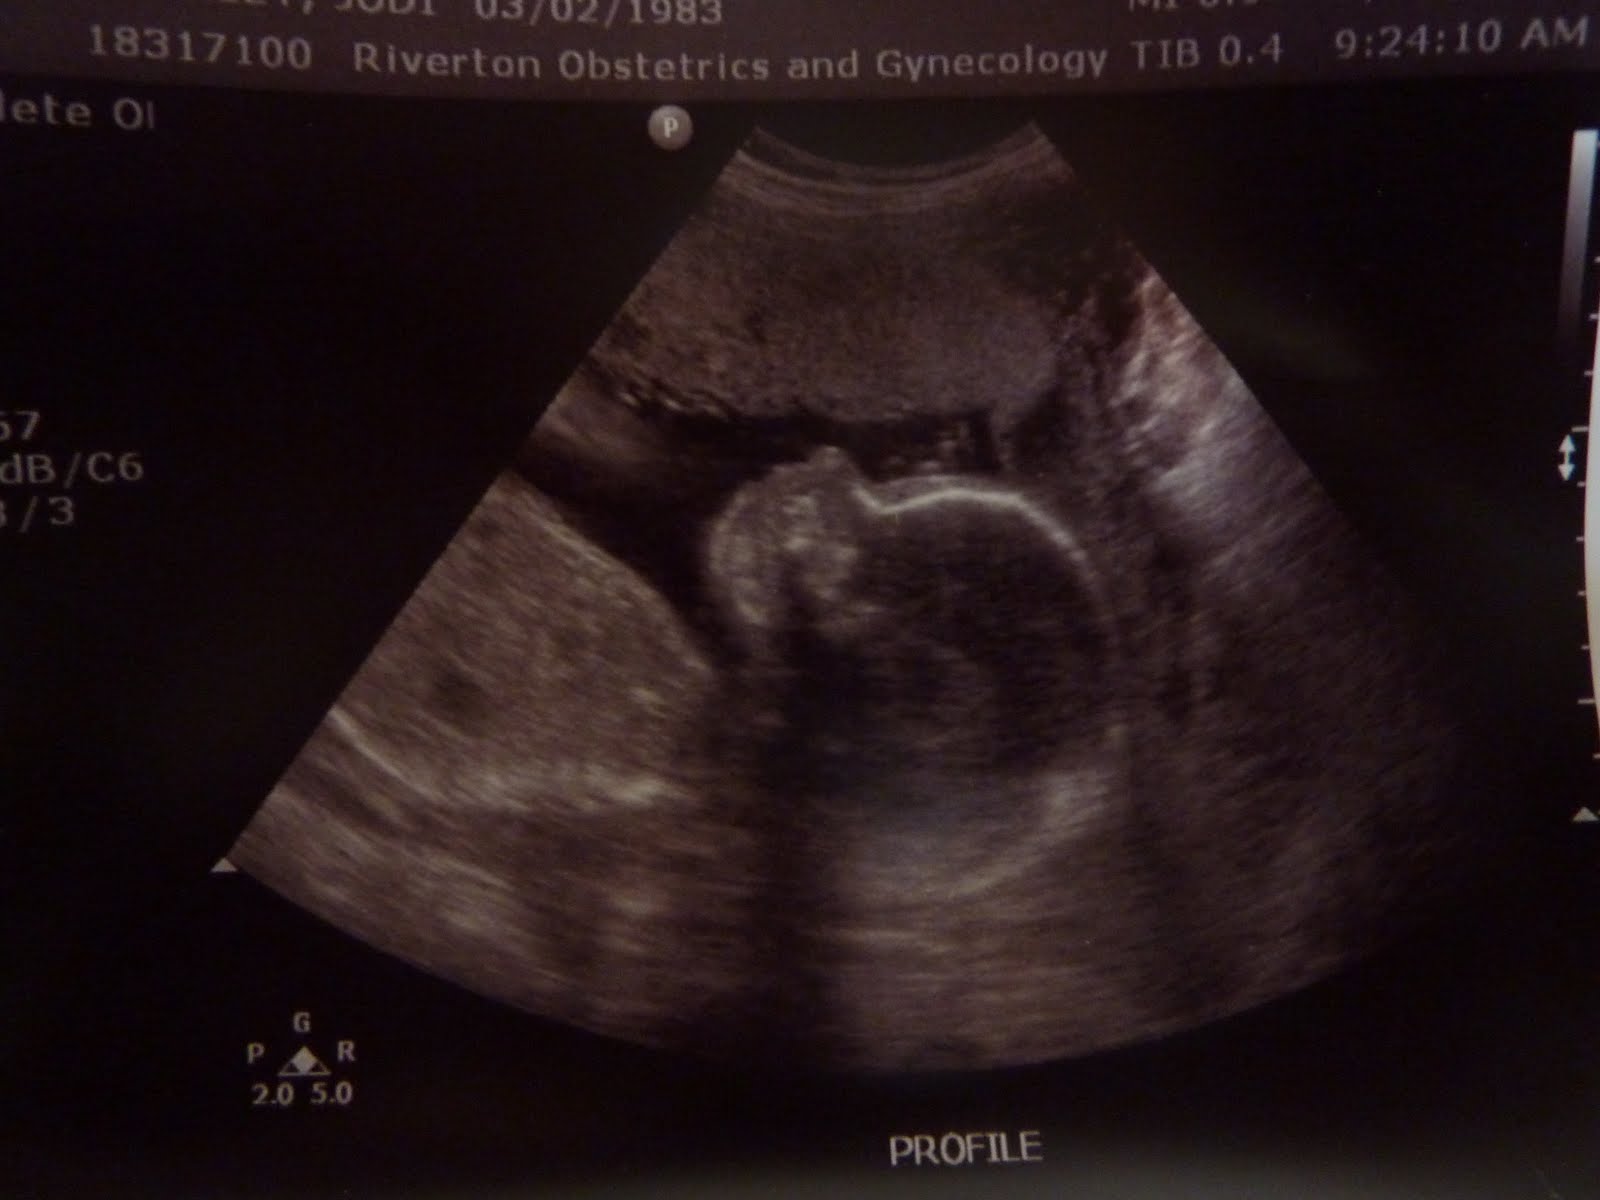

So I definitely have a lot of catching up to do...I have been a slacker when it comes to blogging. I am now 8 months pregnant about seven weeks left and starting to count down. They say that every pregnancy is completely different and I would for sure say that this one has been compared to Mylee. First trimester I was really sick, very tired, and started showing a lot faster. I quickly realized that because I had Mylee plus working at nights and on weekends my energy was shoot. After about 17 weeks definitely started feeling better and had more energy. We were really excited to find out what we were having from the beginning I would say both Jesse and I kept thinking a boy and Mylee always told me it was going to be a boy, the morning we went to find out I asked Mylee what if the Doctor tells us its a girl? She said no she will tell you its a boy, and she was right. We are really excited to have a little boy although its a little weird to think about because i am so used to everything being all girl. Jesse was super excited and couldn't wait to start texting and calling everyone to let them know.

From our twenty week ultrasound appointment we got some worrying news, they had told us they found a hole in the baby's heart which could mean a couple of things if it was small enough it would possibly be able to mend on its own or if it was big enough the baby would have to have open heart surgery as soon as he was born to fix it. So needless to say it was very stressful, we had to go about 5 weeks later to primary children to have a fetal echo done to determine exactly how big the hole was. Very nervous we went in and left with a extremely grateful hearts because everything came back normal, there was no hole and everything looked great. With that under our wing we then found out that the baby only has one kidney and I have only a two vessel umbilical cord instead of a three. Which the vessels are what provides nutrition to the baby. So I have and have had to go in to a specialist every four weeks for an ultrasound where they do all his measurements to make sure he is growing and getting what he needs as well as they monitor the one kidney that he has. Many people live with just one kidney as long as the one they have is healthy and normal so they have been keeping track of the one he has. Once he is born we will have to see a urologist to do ultrasounds on the baby to make sure the one he has is good. So far the baby as been measuring right on track which is been great news meaning that hopefully he is getting what he needs. Although this has been very stressful, it has definitely made me realize the importance of prayer and priesthood blessings and that i need to rely more on these things.

We are anxious to meet our little guy and pray he is healthy and have faith that things will all be okay.